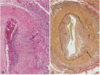

What is this an example of?

This is Monckeberg medial calcific sclerosis with the collection of calcium deposits (arrows) in the media of small muscular arteries